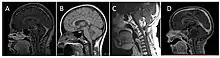

| Brain stem glioma. MRI axial, with contrast | |

_-_Fonc-02-00205-g003_D_(cropped).jpg.webp)

Neuroimaging, such as MRI, is the main diagnostic tool for brain stem gliomas. In very rare cases, surgery and biopsy are performed.